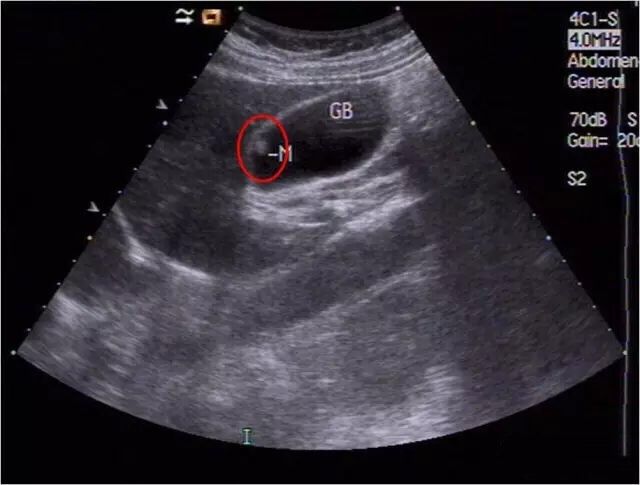

1、消化系统:肝胆胰脾的超声检查。

4、胸腔、腹腔积液、肿块的超声诊断。